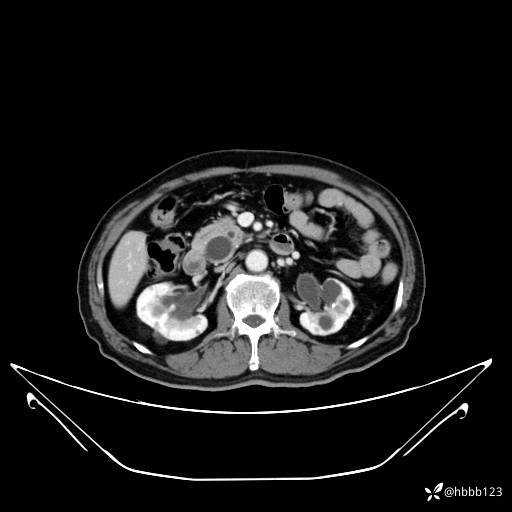

延迟期: